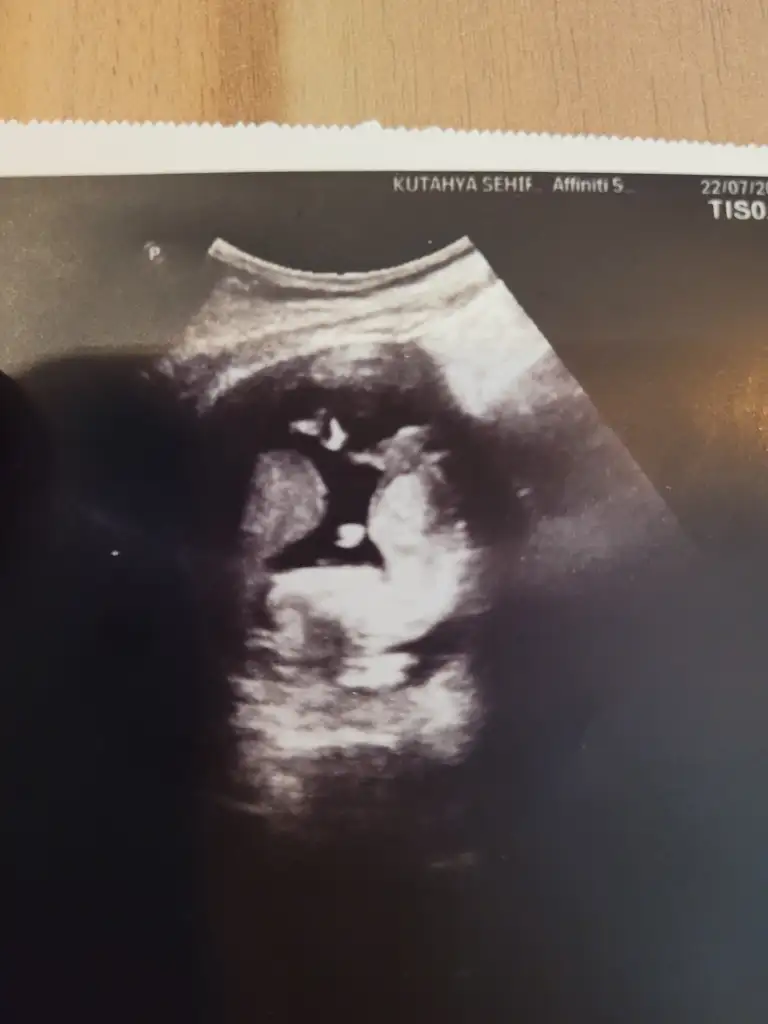

Yorum yaparmısınız. Biri 11hafta 6günlük. Diger 16 haftaKızzzz

kızYorum yaparmısınız. Biri 11hafta 6günlük. Diger 16 hafta

Erkek gibi geldi banaYorum yaparmısınız. Biri 11hafta 6günlük. Diger 16 hafta

Sizinde erkek

Erkek :) givi duruyor ama Allah gönlünüzdekini versinYorum yaparmısınız. Biri 11hafta 6günlük. Diger 16 hafta